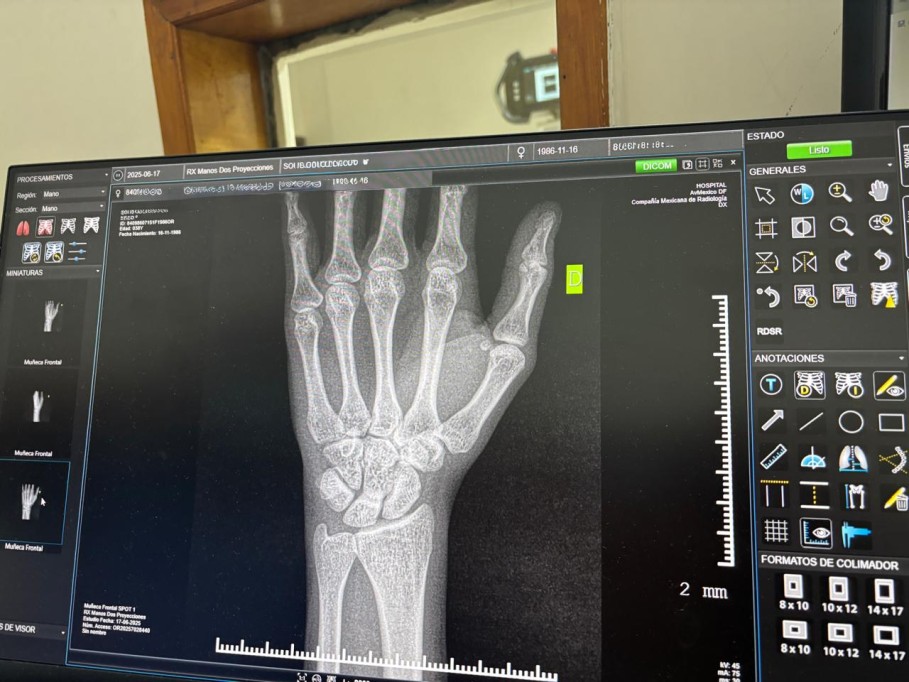

Estas condiciones debilitan la estructura esquelética y elevan el riesgo de fracturas, presentándose frecuentemente de forma asintomática en sus etapas iniciales.

El especialista señaló que es necesario solicitar valoración médica profesional ante síntomas como dolor persistente sin causa aparente, fracturas recurrentes o una disminución progresiva de la estatura.